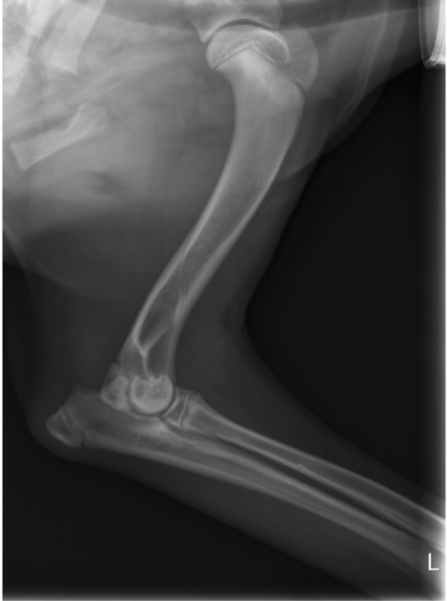

Aaron war munter und aufmerksam, sein Herz-Kreislauf-System und die Palpation des Abdomens waren unauffällig. Seine innere Körpertemperatur lag mit 38,9°C im physiologischen Bereich. Er ging hochgradig lahm auf der linken Vordergliedmaße. Bei der Palpation des linken Vorderbeines konnte man eine deutliche Gelenkfüllung und eine Schmerzhaftigkeit des Ellbogengelenks feststellen. Alle anderen Gelenke waren frei beweglich und nicht schmerzhaft. Es wurde eine Röntgenuntersuchung beider Ellenbögen und Schultern durchgeführt. Die Schultern stellten sich röntgenologisch völlig unauffällig dar. An beiden Ellenbögen konnten Veränderungen in Form einer  Osteochondrosis dissecans (OCD = Knorpelveränderung) nachgewiesen werden, und der linke Ellbogen war hochgradig verdächtig für eine Ellbogendysplasie (ED) mit einem Frakturierten Processus Coronoideus medialis (FCP= abgebrochenes Knochenteil). Aufgrund der röntgenologischen Befunde wurden beide Ellenbögen arthroskopiert. Der Verdacht einer Ellbogendysplasie konnte in der Arthroskopie bestätigt werden. Das abgebrochene Knochenteil wurde entfernt und die Knorpelschuppen der OCD beidseits abgetragen.

Osteophytäre Zubildungen (Arthrosen) wurden am Gelenk diagnostiziert

In den nächsten Tagen erhielt der Hund ein Schmerzmittel und Hyaluronsäure zum Knorpelaufbau und ging regelmäßig zur Physiotherapie. Aaron lief vier Wochen lahmfrei ohne Schmerzmittel. Danach ging er wieder zunehmend lahm. Er zeigte wieder deutliche Gelenkergüsse in beiden Ellenbögen. Es wurde eine Computertomographie-Untersuchung (CT) beider Ellenbögen durchgeführt. Im CT wurden mehrere osteophytäre Zubildungen (Arthrosen) am Gelenk diagnostiziert, welche infolge des permanenten Entzündungsreizes entstanden sind. Weitere knöcherne Veränderungen und eine erneute abgelöste Knorpelschuppe (OCD) konnte nicht gefunden werden.